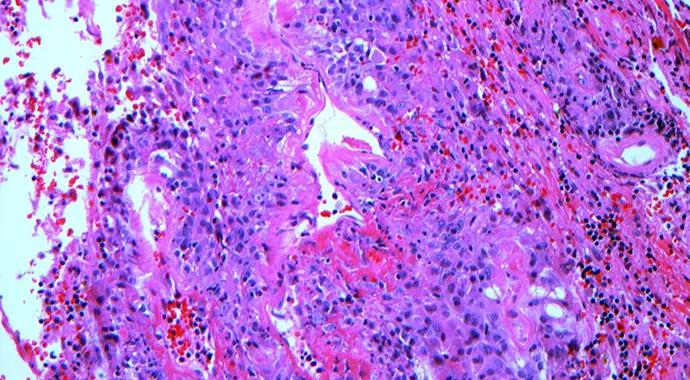

An 11-year-old girl diagnosed with Takayasu arteritis developed severe stenosis of the left renal artery and superior mesenteric artery, resulting in hypertension and intestinal angina (Figure 1). Despite aggressive and appropriate immunosuppression by her local pediatric rheumatologist, the stenosis worsened and her uncontrolled hypertension, which was unresponsive to numerous antihypertensive medications, resulted in posterior reversible encephalopathy syndrome and heart failure. She was eventually transported to Cleveland Clinic Children’s by fixed-wing aircraft from the Cleveland Clinic Critical Care Transport fleet for further evaluation.

Figure 1

In collaboration with the Center for Pediatric Rheumatology, our vascular surgeon performed autologous bypass grafts to correct the diminished perfusion that was causing the patient’s symptoms. She tolerated the procedure well and had significant improvement in her heart function, blood pressure and intestinal angina, which allowed us to reduce the intensity of her immunosuppressive and antihypertensive regimens.